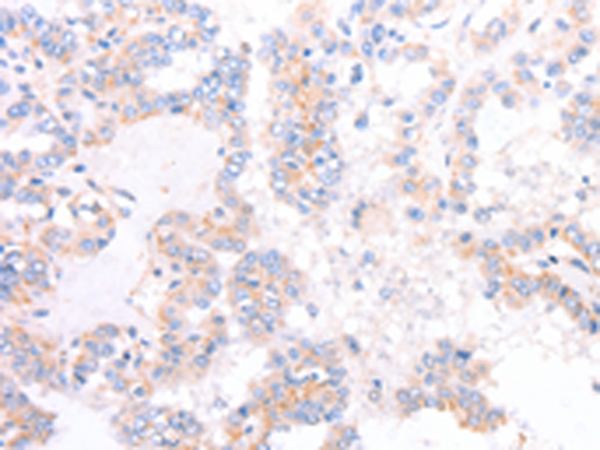

分类: 科研抗体货号: P06989别名: CPP32; SCA-1; CPP32B应用: WB,IHC反应种属: Human, Mouse, Rat